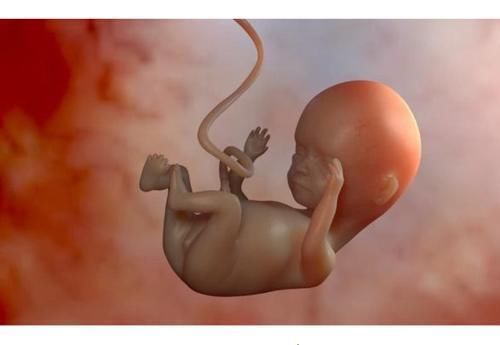

在怀孕的第十个月,怀孕的母亲都对喉咙紧张提到了自己的心脏,许多人对此感到好奇。怀孕十个月,子宫内没有任何黑暗。每个人都错了,胎儿正忙于自己的事。

实际上,许多人认为,胎儿出生时,胎儿只能喂养,呼吸和玩耍。实际上,婴儿还在肚子里的时候就已经“忙”起来了,他慢慢地做了很多事情。

胎儿很小时就不进食,子宫内也没有食物。但是,胎儿可以通过与母亲相连的脐带吸收营养。排泄物也通过脐带传递给母亲,并由母亲代谢。“呼呼”也将在子宫内吸收和吸收营养。

当受精卵缓慢发育成胎儿时,神经和各种器官发育缓慢。因此,当胎儿是第一个人类时,它已经有睡眠,但是在早期阶段,睡眠时间更长,这时胎儿需要的睡眠越来越少,此时胎儿的运动会越来越频繁。

许多怀孕的母亲在进行4D拍摄时发布了自己的照片,发现婴儿的动作“奇妙”,有些会“食指”,有些在“笑”,并且婴儿在玩脐带。当然,这是正常现象。

妊娠晚期胎儿的频繁运动也是由于婴儿活动的增加。实际上,这是婴儿发育的信号。频繁的胎儿运动也表明婴儿即将“出来”。